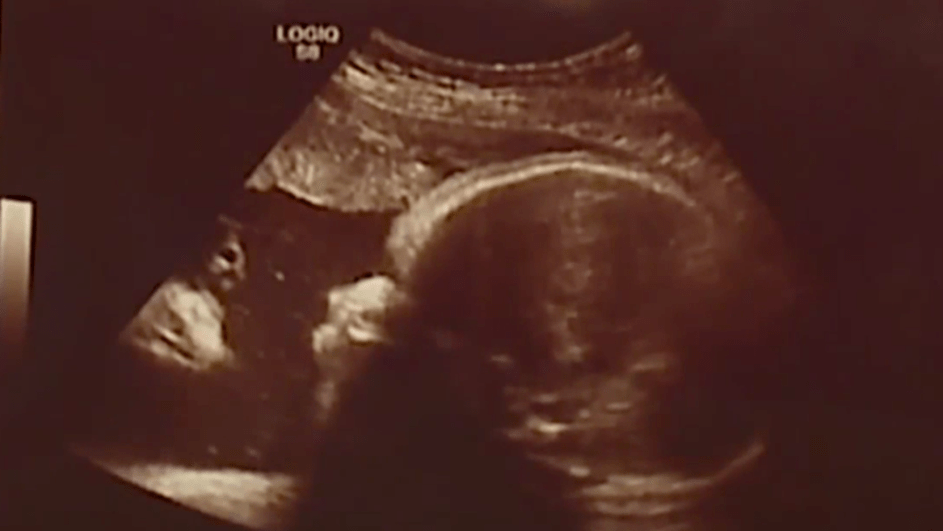

Slika ultrazvuka iznenadila je buduće roditelje: ‘Što je to?!’

OSTALO

RELIGIJA

26.08.2017.